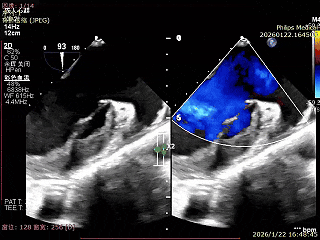

术前超声影像

左室长轴超声可见大量反流

可见二尖瓣明显反流